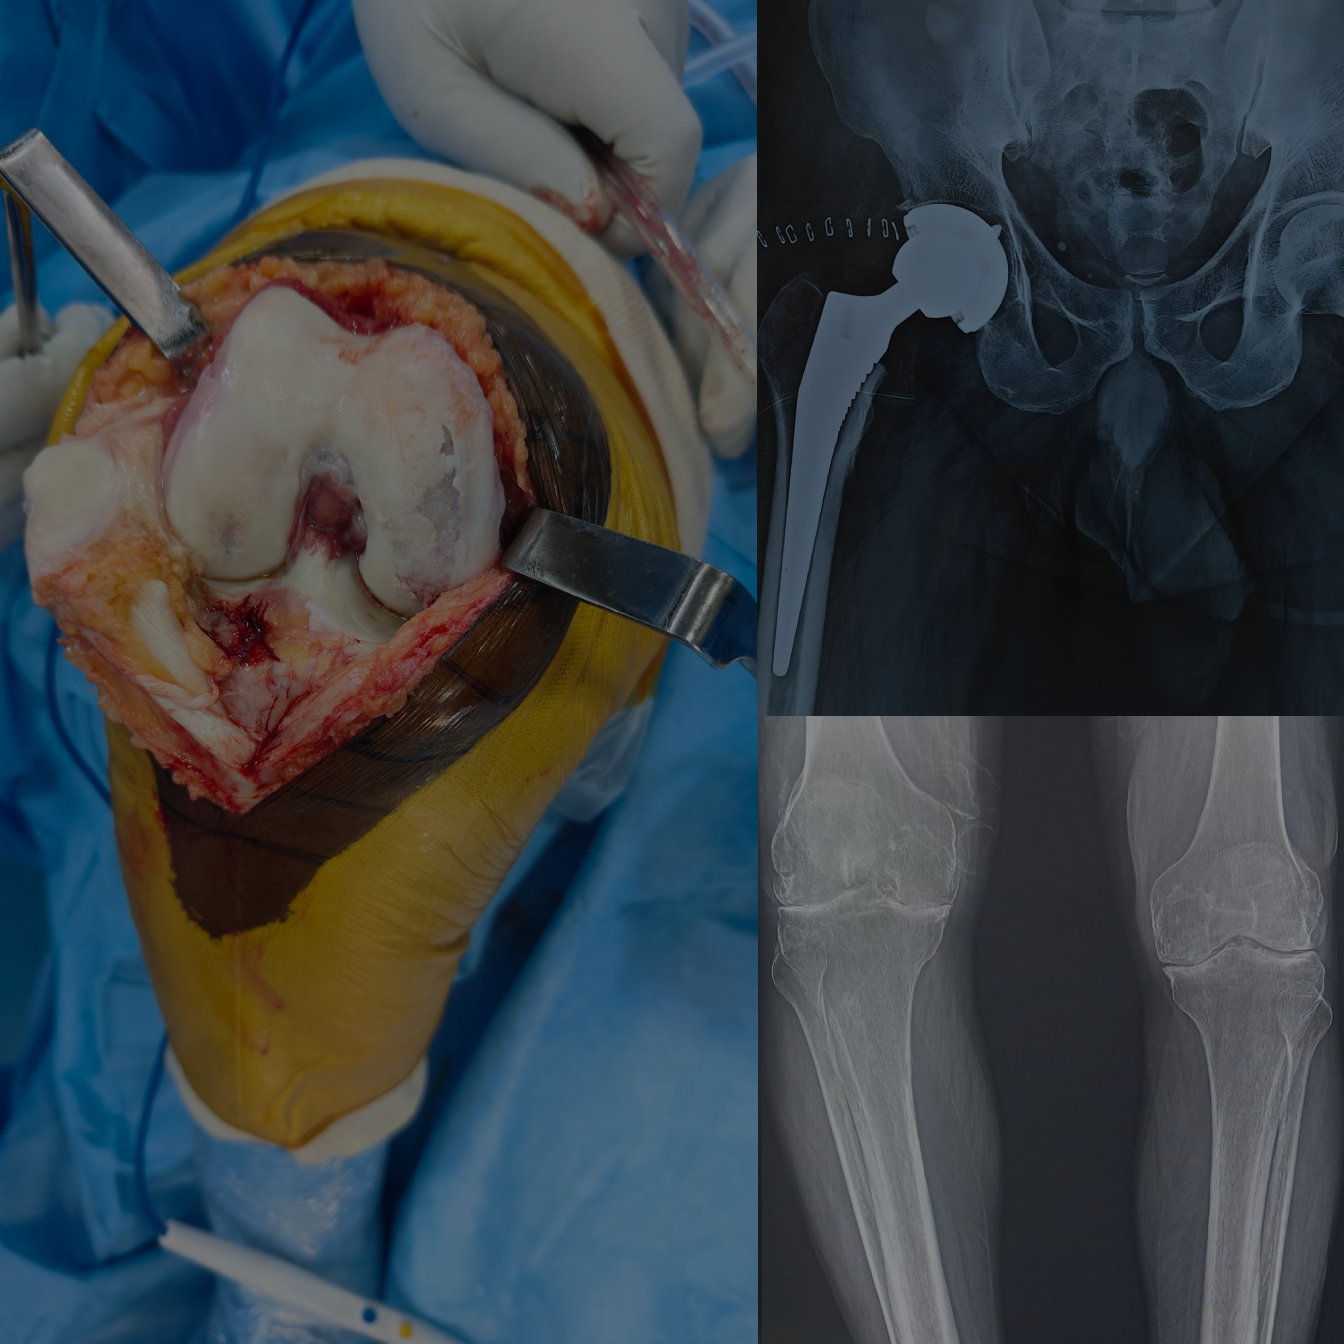

Step Back into an Active Life with

Professional Orthopedic Care for Bones, Joints and Spine

Supporting healthy bones, joints and spine with care that reduces pain and improves everyday movement, helping individuals stay active and mobile.